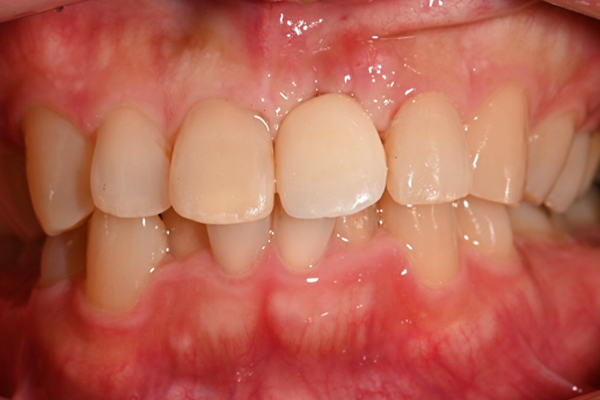

| 主訴 | 前歯がぐらつく |

|---|---|

| 治療内容 | 左上前歯に対するインプラント治療 |

| 治療期間 | 3ヶ月 |

| 治療費 | 41万5千円 |

| 治療 リスク | 最終的な歯が入るまでは仮歯になります |